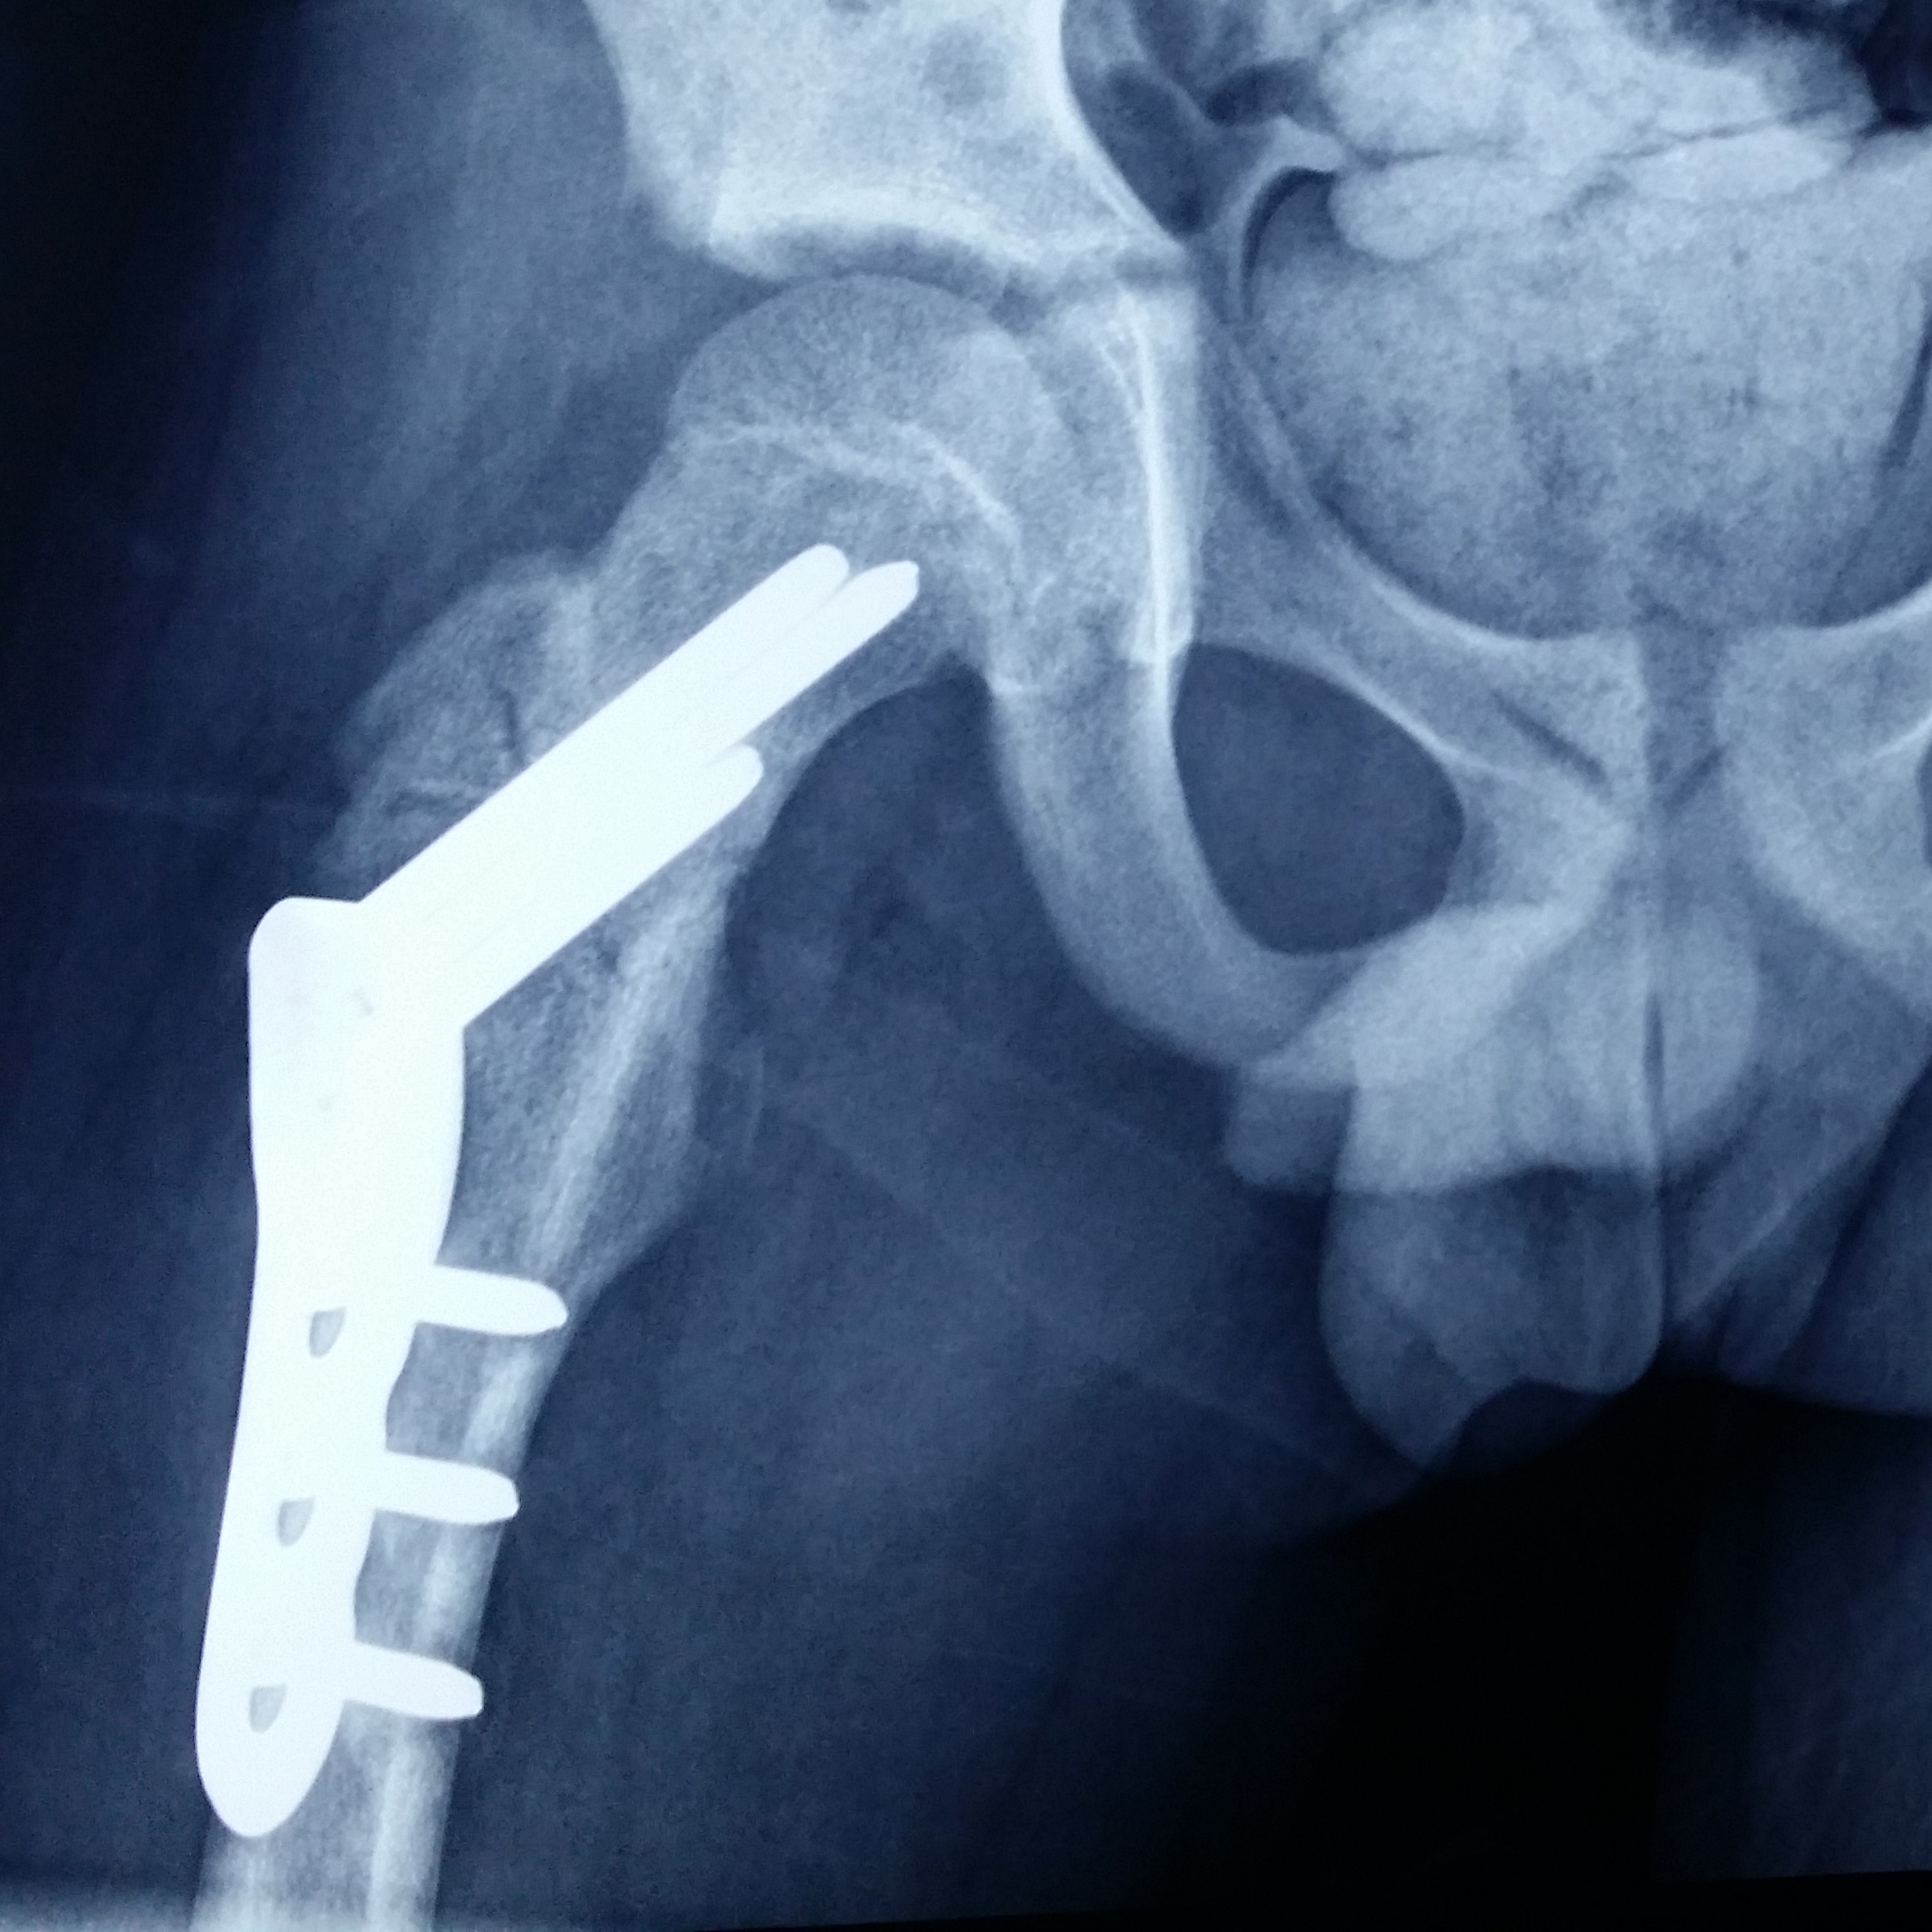

Fracturas

La Traumatología Infantil comprende el tratamiento de lesiones traumáticas del aparato locomotor (fracturas, luxaciones, esguinces).

Fracturas, esguinces y luxaciones de todo tipo, incluyendo accidentes caseros - escolares - de tránsito, así como lesiones deportivas.